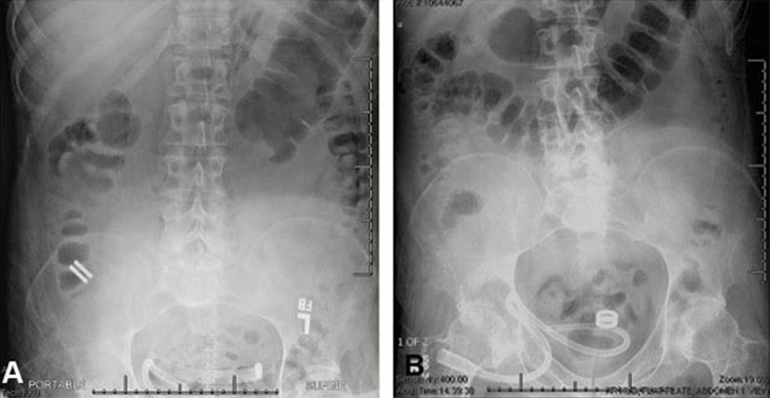

The study, led by Principal Investigator Michael Harrison, MD, is a prospective, single-center, first-in-human pilot clinical trial to evaluate the feasibility and safety of creating an intestinal anastomosis using the Magnamosis device. Magnetic compression anastomosis (magnamosis) uses a pair of self-centering magnetic "Harrison Rings" to create an intestinal anastomosis without sutures or staples. Each magnet is placed within the lumen of a desired segment of the intestine and brought together, or “mated.” The magnetic force on the compressed tissue causes necrosis and an anastomosis forms. The magnets then pass through the bowel.

The Magnamosis device's method of slow tissue remodeling without leaving foreign bodies creates a well-formed anastomosis, which can decrease the incidence of anastomotic leaks. In addition, the simplicity of merely “sticking” the 2 segments of intestine together can save substantial operative time. However, open operation is not the best way to showcase the merits of magnamosis. In our subsequent patients, we plan to focus on laparoscopic delivery of the Magnamosis device, which currently can be deployed using laparoscopic, endoscopic, radiographic, or hybrid techniques. In addition, the device can be sized and adapted to a variety of intraluminal anastomoses, including intestinal, urologic, and biliary applications, with wide-reaching implications for the future of surgery.